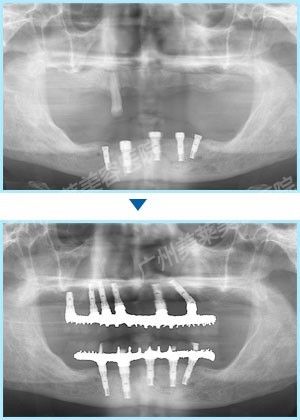

陳回英阿姨在美萊 手術(shù)完成了全口16顆牙種植過程

根據(jù)方案,廣州美萊為陳阿姨上下各種植了8顆牙,手術(shù)中采用即拔即種、植骨、蓋膜、上頜竇提升技術(shù)同步進行,這樣可確保種植后她能恢復全口真牙的咬合功能,吃東西完全沒有問題。 手術(shù)完成了全口16顆牙的種植!